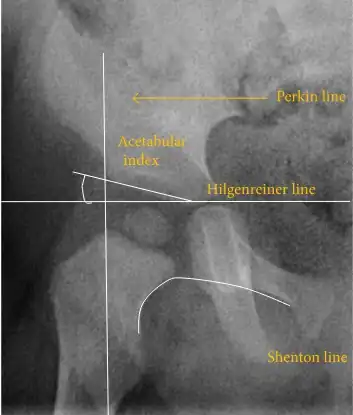

The most useful lines and angles that can be drawn in the pediatric pelvis assessing hip dysplasia are as follows:[50] Different measurements are used in adults.[50]